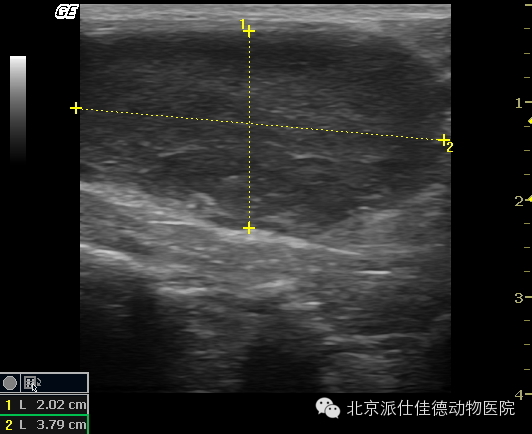

5.有些动物表现为排尿困难,X线片和B超也没有发现结石,经诊断发现是前列腺肿瘤。